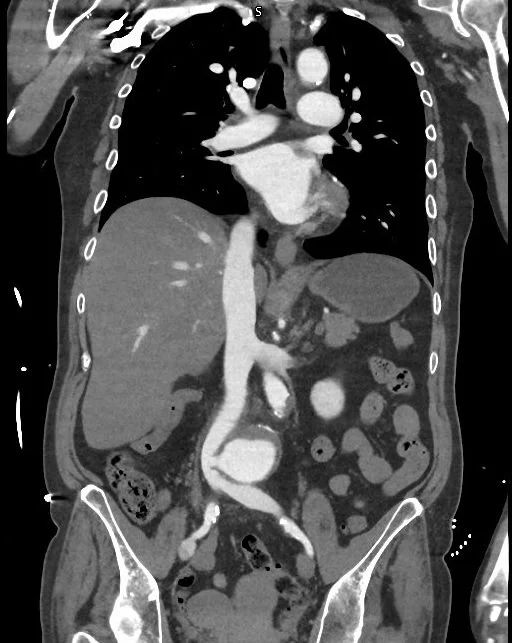

Sheperdigian says a consult and surgery with Franco Rea, MD, saved her life. The culprit, illuminated by the CT Sheperdigian ordered and shown below: an aortocaval fistula.

‍An ACF is a rare, life-threatening complication in which an abdominal aortic aneurysm erodes into the adjacent inferior vena cava, causing a direct, high-pressure shunt between the two vessels. Immediate surgery is required, as untreated cases have a near 100-percent mortality rate, according to NIH.